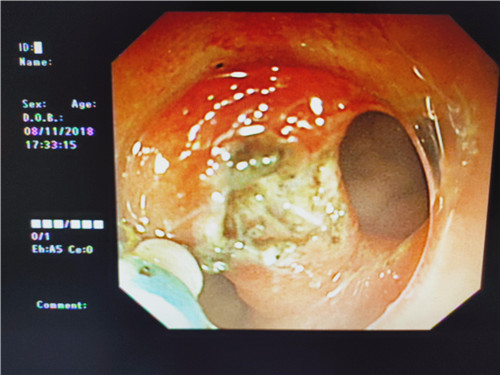

在检查过程中,当曹鹏主治医师将内镜进至吻合口狭窄处时,却偶然发现狭窄部位旁边还有一小小入口,探镜而入,发现这条小小隧道与狭窄部一同通向肠腔,中间相隔了一条不宽不窄的“桥梁”,把本来通畅的“大路”隔成了两条幽径小道,因此患者排便才会堵塞不通。经过反复观察,仔细斟酌后曹鹏医生萌生了,把“桥梁”拆掉,使“曲径小路”变“宽敞大道”的想法。因为这时如果按原计划行肠镜下吻合口扩张术已经没有太大的意义,但肠道薄弱容易造成穿孔,“桥梁”处是否有大的血管,存在出血、穿孔的风险等等,这些都需要与主管医生进一步探讨。随即他与普通外科史和平主任,消化内镜室王莹主任会诊后决定实施“粘膜桥离断术”(ESD内镜下粘膜剥离术)。将术中风险及意外向患者及家属充分告知后,征得患者家属同意签字,随后便开始施行手术。在史主任、王主任、李侠护士长的支持保驾护航之下,曹鹏医生以精湛的医疗技术,与护士的默契配合,顺利完成了手术,术中无出血、穿孔,眼前显示器屏幕上出现了预期中的“宽敞大道”,手术成功了!大家原本绷紧的面容出现了笑容。患者从此以后不会再有排便不畅的痛苦了,患者唐某及家属,欣喜及感激之情溢于言表,医生们再一次为他解决了一件大事情,患者术后恢复良好。